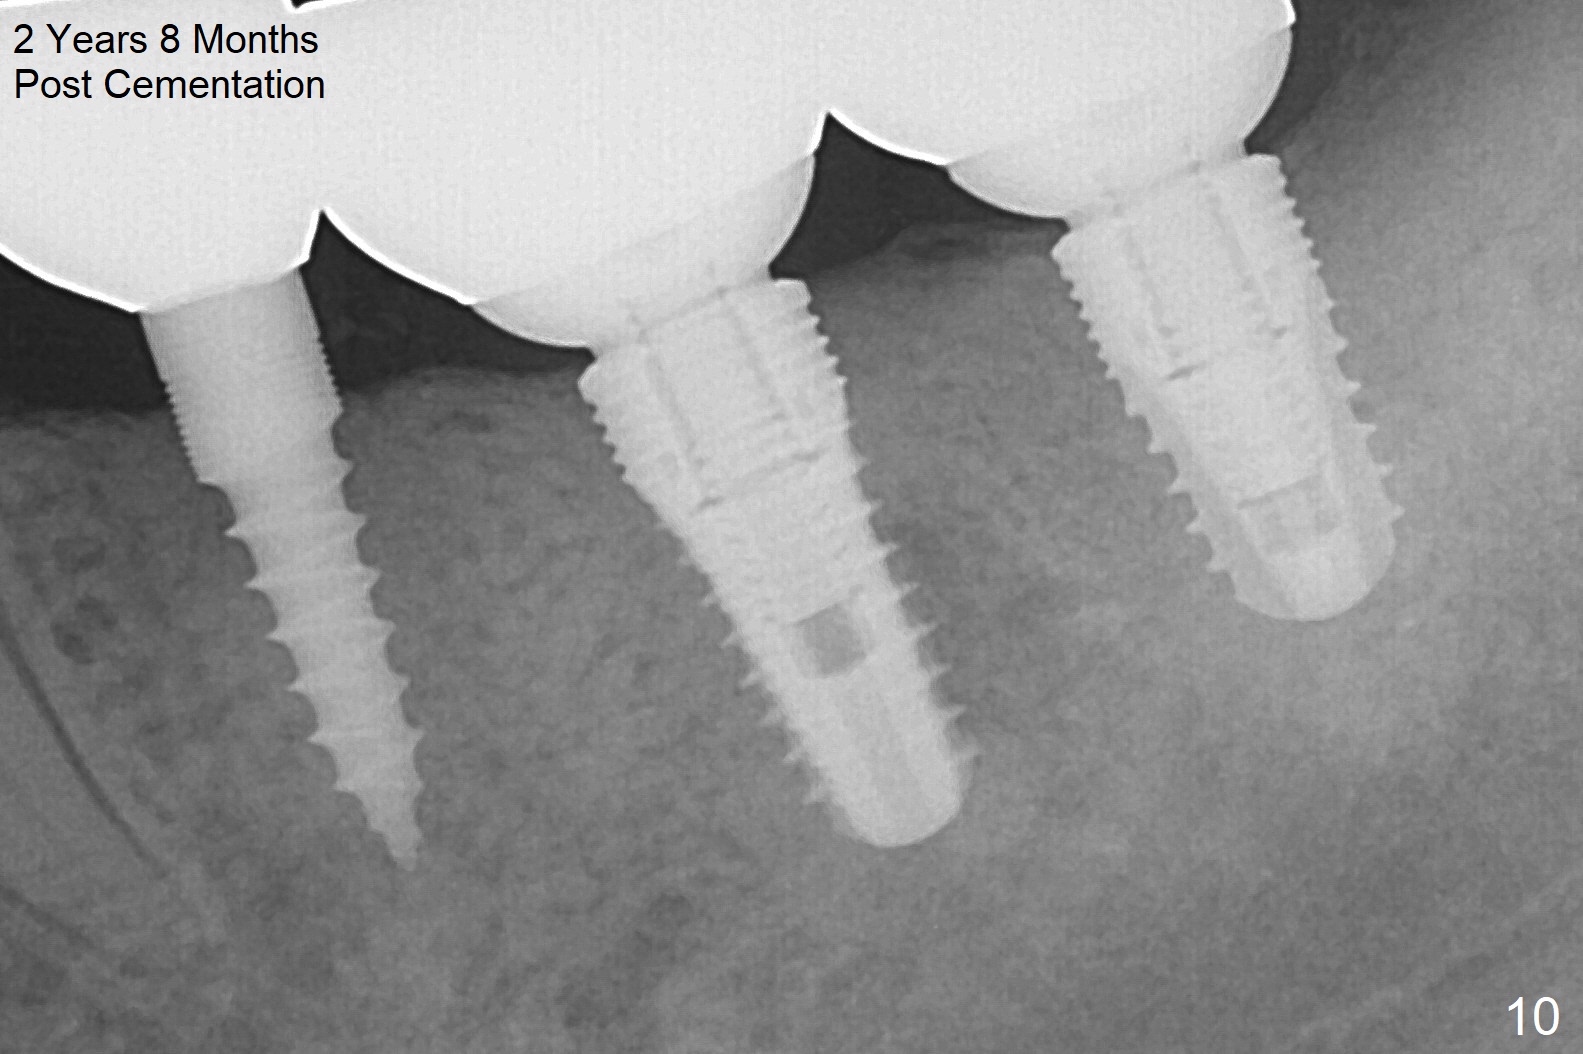

The patient is doing well postop, but 1 month postop, she complains of pain in the left submandibular area. When the immediate provisional is removed, the gingiva between the implants is erythematous (Fig.5 ^). The provisional is modified with accentuated grooves between the margins of the implants (Fig.6 *) with oral hygiene instruction. In fact the provisional is not cemented so that it is easy for self cleansing. There is crestal bone resorption 3 months postop (Fig.7,8). No further bone loss 1 year post cementation (Fig.9, cropped from pan). The bone density around the implants increases 2 years 8 months post cementation (Fig.10).